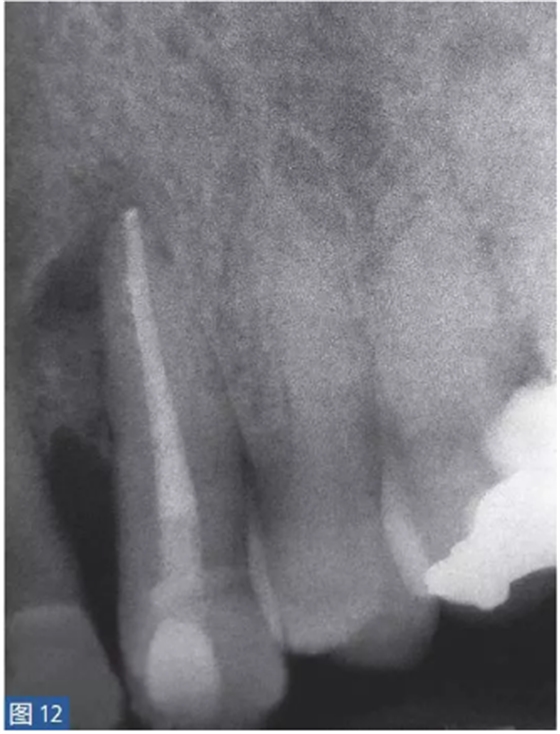

根尖周囊腫伴無癥狀性根尖周炎(AAP)

根尖周囊腫(圖12 和13)總是與無癥狀的根尖周炎相關(guān)。目前普遍認(rèn)為,通過上皮殘留細(xì)胞的炎性增殖形成了根尖周囊腫。在組織學(xué)上,它們分為袋囊腫(pocket cyst)和根尖周真性囊腫(periapical true cysts)。通常認(rèn)為,袋囊腫可以通過單純的根管治療而非手術(shù)方式,即通過細(xì)胞凋亡(apoptosis)和程序性細(xì)胞死亡(programmed cell death)達(dá)到愈合。這種方式在真性囊腫似乎不太可能實(shí)現(xiàn)。

圖12: 23 牙齒根尖周囊腫 。非手術(shù)治療,采取單純的根管治療后的X 線片檢查。因未愈合而決定采取手術(shù)治療。

圖13:手術(shù)性根管治療一年后的對(duì)照X 線片顯示根尖病灶已愈合。對(duì)搔刮出的組織進(jìn)行組織病理學(xué)檢查顯示為真性根尖周囊腫。